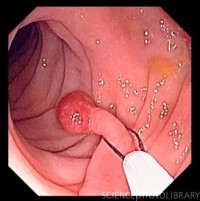

О лечении ПОЛИПОВ

Эндоскопическая профилактика рака

О полипах толстой кишки

Полипы и аденомы по своей сути являются опухолями кишечника.23.06.25

Клиническое наблюдение >>>